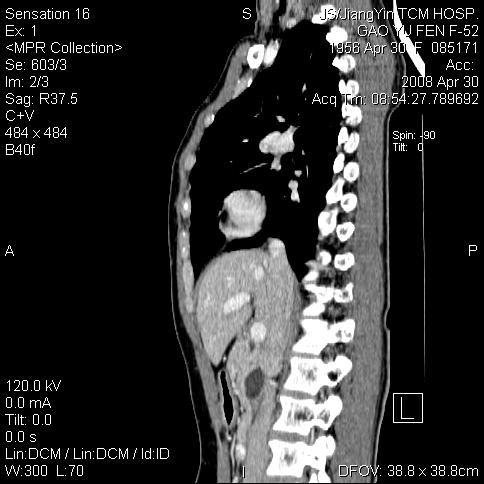

标题: CT13307:肠系膜囊肿? [打印本页]

标题: CT13307:肠系膜囊肿?

支持来源于腹膜后。

图像少,不能连续起来看,不太敢确定囊肿前方的条状结构是十二指肠水平段?如果是,那肠系膜囊肿,淋巴管瘤都有可能。

病变位于肾静脉后方,支持腹膜后占位性病变,以囊性淋巴管瘤可能性大.